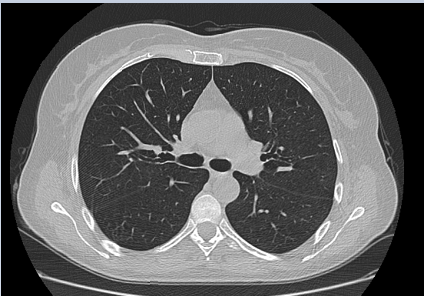

This patient was a 50 years old woman with an invasive ductal G2 carcinoma of the right breast staged pT2 pN0 M0 with Luminal A phenotype. Anamnesis was negative for diabetes, opportunistic infections, autoimmune diseases. After conservative surgery, she had Tamoxifen and underwent adjuvant RT with 3dimensional conformal technique and conventional fractionation (2Gy/50Gy) plus a 10 Gy boost on the tumor bed. Radiation treatment plan consisted of two Multi leaf Collimator customized 6 MV tangential fields depicting a typical dose distribution around the right breast. The right lung V20 Gy was <20% and MLD was <8 Gy. During the treatment, no acute toxicity was recorded; the patient completed the RT treatment at the end of January 2020. Two months later, the patient returned to our observation complaining of a flu-like syndrome, cough, fever, moderate-severe dyspnea due to an acute pneumonitis. The CT scan images showed in the upper right lobe some areas of consolidation resembling pneumonia and in both lungs many ground -glass opacities with the bronchus sign (Figure 1). Swab and RT-PCR were negative for CO-19; the specific serology and BAL confirmed the absence of the virus infection. BAL consisted of inflammatory cells showing many neutrophilis and activated lymphocytes. The virus was not detected after steroid assumption, the symptoms drastically ameliorated. The CT scan showed a complete resolution of the previous findings in both lungs; (Figure 2). The final diagnosis was BOOP.

Figure 1 CT scan of the chest at baseline.